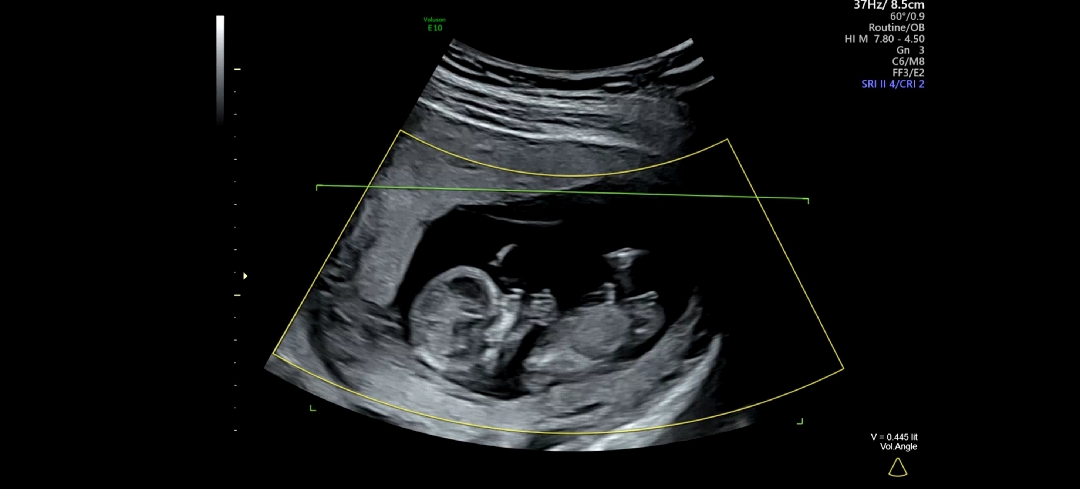

고수님들 성별 봐주세요(니프티 결과 기다리는중/후기 남길게요)

어제 니프티 검사를 했지만 너무 궁금해요! 결과 나오면 후기도 올릴게요 고수님들 어떤지 봐주세요~ ‐------------------------------------ 결과 나와서 글 새로 올렸습니다!

아들에 한표던졌습니다